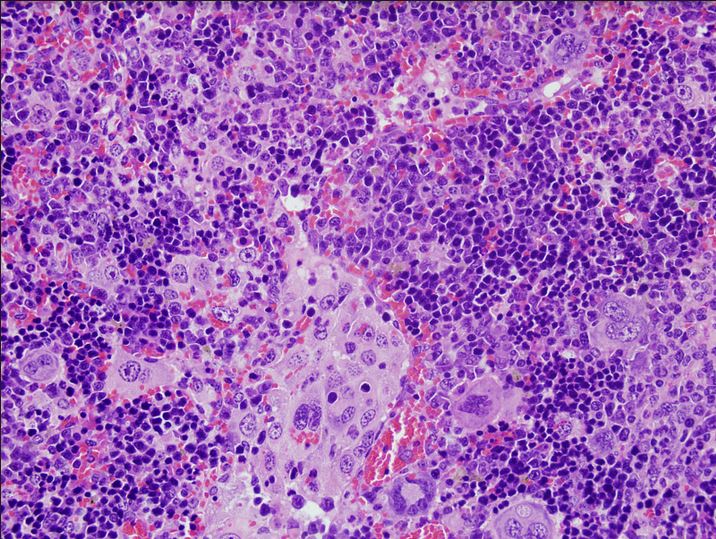

Imagen de microscopía del bazo de un ratón que ha desarrollado un linfoma periférico de células T a causa de alteraciones en el gen VAV1

En el trabajo se ha desarrollado también un modelo animal que permite generar linfomas en ratones tras la expresión de mutantes de VAV1 en linfocitos T sanos. Usando técnicas genómicas y bioinformáticas, se ha podido comprobar que estos linfomas reproducen la gran mayoría de las características clínicas, patológicas y moleculares de los linfomas periféricos de células T de pacientes. También ha permitido descubrir talones de Aquiles de estos linfomas que, a partir de ahora, servirán para buscar vías para atacar y destruir este tipo de linfomas. Estos modelos animales supondrán también una vía excepcional, a partir de ahora, para probar a nivel pre-clínico fármacos que se desarrollen contra dichos linfomas